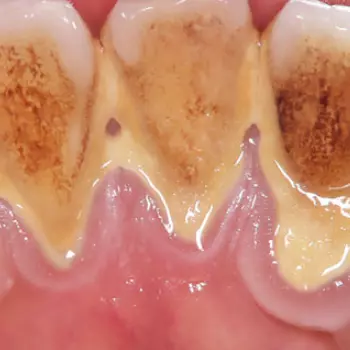

치석 이란, 치구(플라크)와 타액에 포함된 인산이나 칼슘, 음식물 찌꺼기 등이 결합해 치아에 달라붙어 석회화된 것입니다.

치석은 약 80%가 인산칼슘이고 그 외에 단백질이나 탄수화물, 세균의 시체, 음식물 찌꺼기 등이 포함되어 있습니다.

치석은 이름처럼 돌처럼 단단하므로 일반 칫솔질로는 제거가 불가능하며, 치석을 제때 제대로 제거하지 않으면 증상이 악화되어 치은염이나 치주염으로 발전될 수 있으니 적절히 케어해야 합니다.